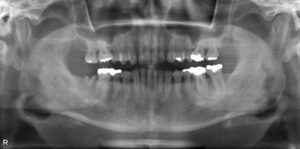

下顎大臼歯1本欠損症例

BEFORE AFTER 45歳男性/下顎1本欠損/インプラント埋込手術 【治療内容】 右下第二大臼歯が残根の状態でご来…